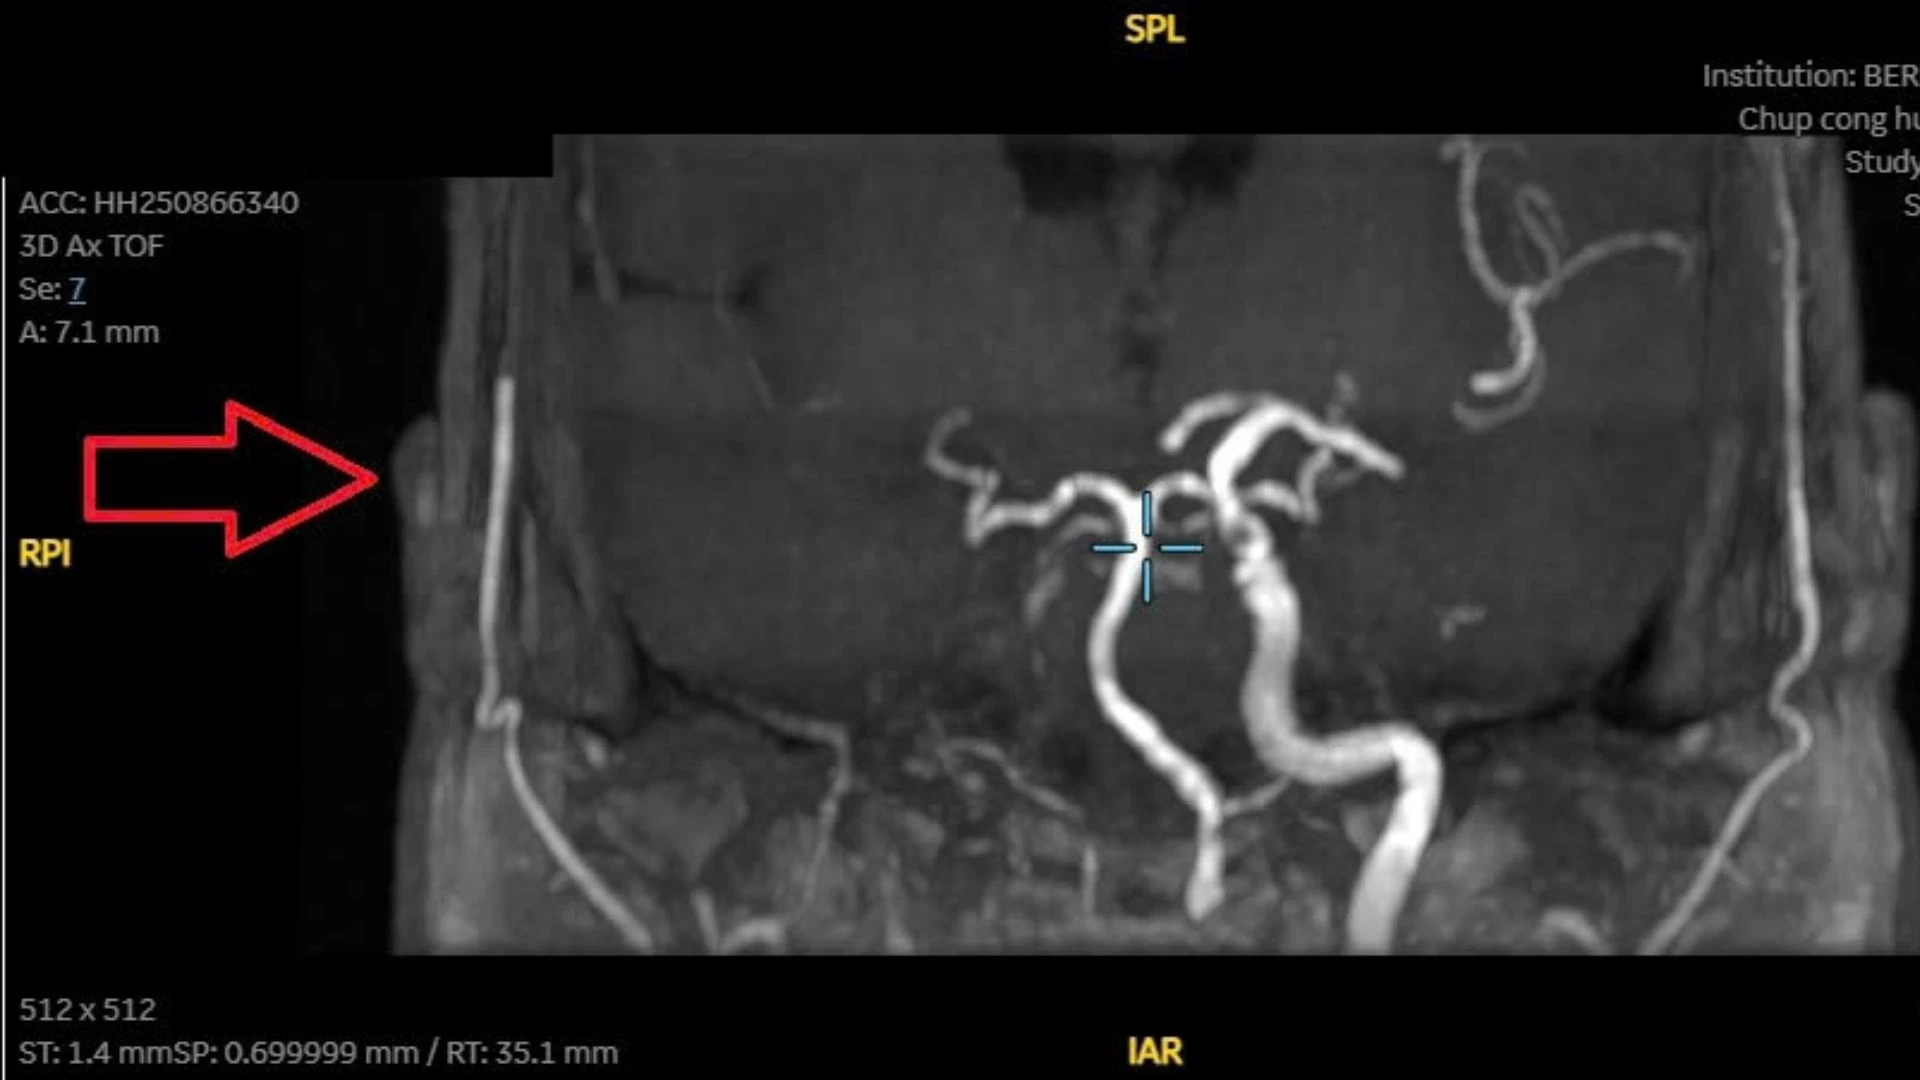

Vấn đề thứ hai là tắc động mạch cảnh trong (P) từ đoạn xương đá thể hiện qua tín hiệu hiệu dòng chảy qua đoạn M1 kém rõ nét. Đây là phát hiện quan trọng, vì tắc động mạch cảnh trong có thể gây đột quỵ thiếu máu não nếu không được theo dõi và xử trí phù hợp.